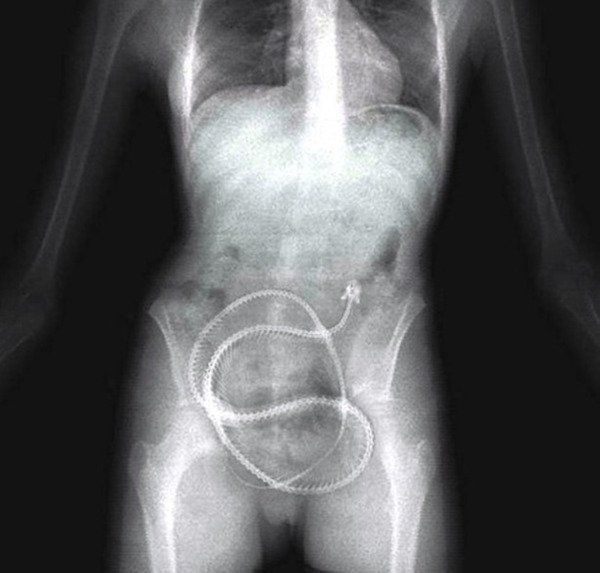

10 / 15Wąż

Jak on się tam dostał?